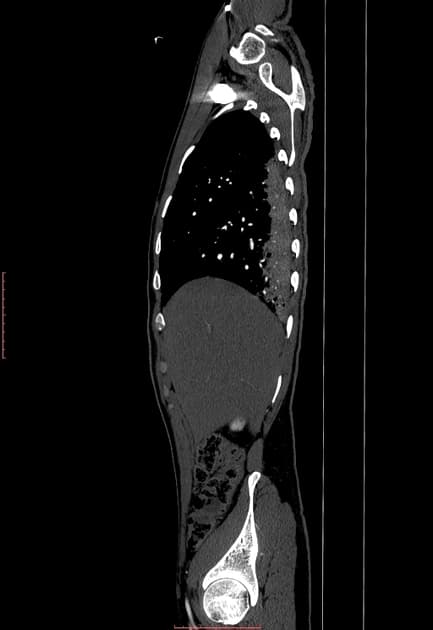

- FLAIR/T2: ghi nhận các tổn thương tăng tín hiệu (hyperintense) ở vùng vỏ - dưới vỏ của hai bán cầu tiểu não (cerebellar hemispheres).

- T1: hai bán cầu tiểu não giảm tín hiệu (hypointense).

- T1 sau tiêm gadolinium: không thấy tăng quang màng não mềm (leptomeningeal enhancement) ở tiểu não.

- Hình ảnh khuếch tán (diffusion-weighted imaging): không thấy hạn chế khuếch tán (no restriction of diffusion).

Viêm tiểu não cấp tính (acute cerebellitis) là một quá trình viêm tại tiểu não, có thể xảy ra như một biến chứng sau nhiễm trùng toàn thân. Một hình ảnh học thần kinh phổ biến là tín hiệu tăng trên T2 (T2 hyperintense) ở cả hai bán cầu tiểu não.

- "Viêm tiểu não cấp tính thường biểu hiện tăng tín hiệu hai bên ở tiểu não trên hình ảnh T2/FLAIR, không hạn chế khuếch tán."